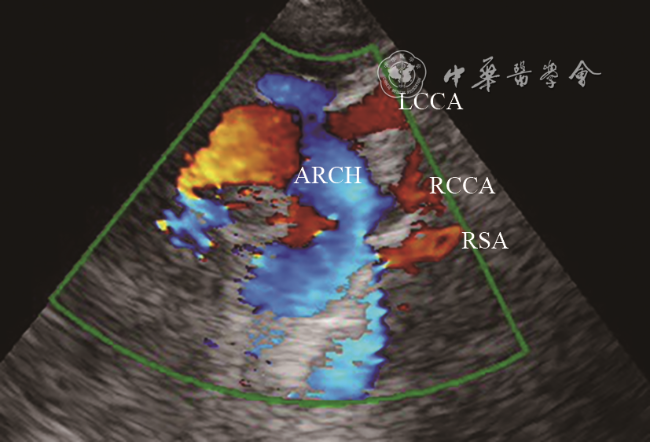

新生儿,足月顺产,Apgar评分9分;产前羊水穿刺正常。2019年10月在成都市第五人民医院分娩后发现左手掌指端紫绀;体格检查:心肺听诊胸骨左缘第二肋间疑似连续性杂音;床旁心脏超声:右位主动脉弓,左位动脉导管未闭,大动脉水平右向左分流。出生后第4天,左手掌紫绀消失。复查心脏超声:心脏房室大小正常,房室连接、心室大动脉连接关系正常;主动脉弓位于气管右侧,弓上可见3个分支,依次为左颈总动脉、右颈总动脉、右锁骨下动脉(图1);左肺动脉起始部可见宽约0.4 cm管型动脉导管未闭,彩色多普勒显示导管内左向右分流(图2);追踪导管走行,导管与左锁骨下动脉延续(动态图1);左锁骨下动脉与主动脉弓无连接关系。进一步行颈部血管超声检查左侧椎动脉,可见椎动脉血流反向(图3)。超声诊断:右位主动脉弓,孤立性左锁骨下动脉,动脉导管未闭,先天性左锁骨下动脉窃血,先天性肺动脉窃血。患儿一般情况良好,于出生后第7天出院,嘱其3个月后复查心脏超声。

图1 孤立性左锁骨下动脉患儿出生后第4天超声心动图胸骨上窝主动脉弓长轴切面显示弓上3个分支

注:ARCH为主动脉弓;LCCA为左颈总动脉;RCCA为右颈总动脉;RSA为右锁骨下动脉

Leutmer等8文献回顾表明,超过半数(59%)的孤立性左锁骨下动脉伴发紫绀型先天性心脏病,其中以法洛四联症(tetralogy of Fallot,TOF)最常见。CT和数字减影血管造影(digital subtraction angiography,DSA)可以很好显示左锁骨下动脉起源以及与主动脉弓的关系,是诊断ILSA的金标准9, 10, 11。本例患儿CTA显示左锁骨下动脉起始端线状变细并靠近左肺动脉,左肺动脉起始部发出鸟嘴样动脉导管残端是孤立性左锁骨下动脉特征性改变。超声心动图可以比较准确地诊断心内结构畸形,但对于不伴心内结构畸形的ILSA超声诊断存在局限性。特别是动脉导管闭合后,由于纵隔遮挡及肺气干扰,很难显示左锁骨下动脉的起源;超声显示同侧椎动脉血流反向有助于提示本病。不过,通过本例患儿发现,新生儿纵隔透声性明显好于成人,使得超声可以更清晰显示主动脉弓上分支起源情况,这有助于明确本病诊断。ILSA患儿胸骨上窝主动脉弓长轴切面,可见异常排列的3个主动脉弓分支,依次为左颈总动脉、右颈总动脉、右锁骨下动脉。当合并动脉导管未闭时,在高位大动脉短轴切面,可以直接显示左锁骨下动脉通过动脉导管与左肺动脉的唯一连接关系。同时,彩色多普勒可以观察椎动脉血流方向以及左锁骨下动脉与肺动脉之间导管内血流分流方向,进一步明确是否存在锁骨下动脉窃血或肺动脉窃血。